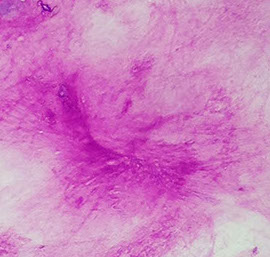

Pleomorphic adenoma

Pleomorphic adenoma (PA)

B9 mixed tumor, MCC salivary gland tumor (1/2-3/4 of all salivary gland neoplasms), painless, firm mass usually growing slowly in tail of parotid at jaw angle

Micro: fibromyxoid background, epithelial (round to columnar cells c uniform round nuclei grouped in honeycomb pattern with frayed edges) and myoepithelial / mesenchymal (myxoid ground substance-secreting single cells that can be spindly, clear, plasmacytoid or epithelioid) cells c chondromyxoid matrix (looks blue like mucin / troll hair) and sometimes tyrosine crystals

- matrix component can be little or appear adenoid cystic

- 1/5 have atypia or metaplasia

Genes: (+) PLAG1 gene alterations pathognomonic

PA

PA - trolls hair